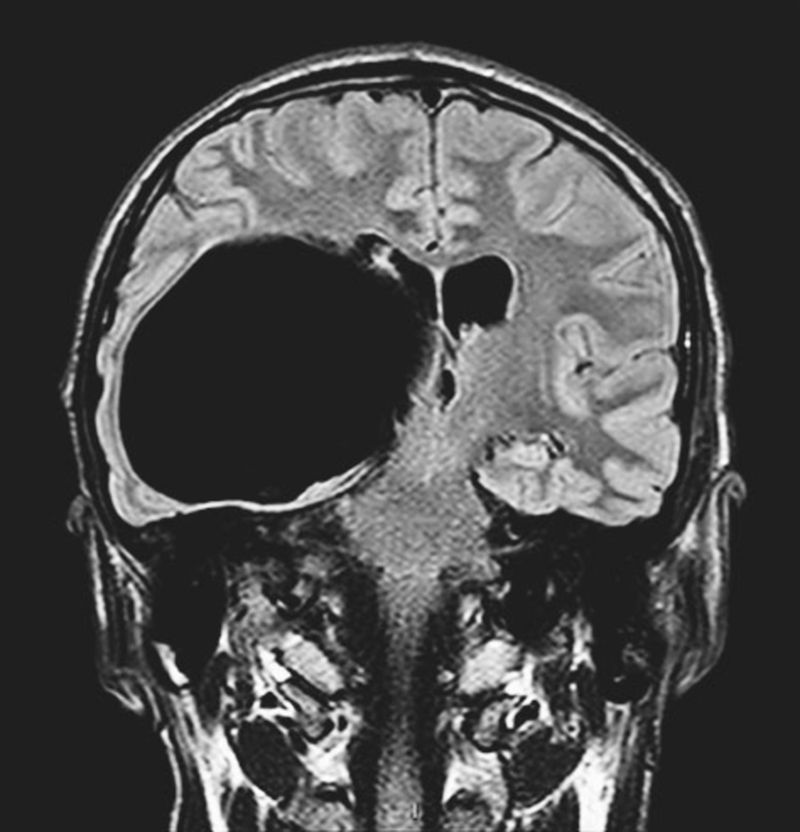

What could be the most likely diagnosis for this incidental finding on an MRI?

Incidental Finding on MRI in a 22-year-old man